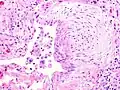

Appearance of honeycomb change in a surgical lung biopsy at low magnification. The dilated spaces seen here are filled with mucin. Hematoxylin-eosin stain, low magnification. A fibroblast focus in a surgical lung biopsy of UIP. Hematoxylin-eosin stain, high magnification. The white space to the left is an airspace. The pale area to the right is a fibroblast focus. It is an area of active fibroblast proliferation within the interstitium of the lung.

A fibroblast focus in a surgical lung biopsy of UIP. Hematoxylin-eosin stain, high magnification. The white space to the left is an airspace. The pale area to the right is a fibroblast focus. It is an area of active fibroblast proliferation within the interstitium of the lung.